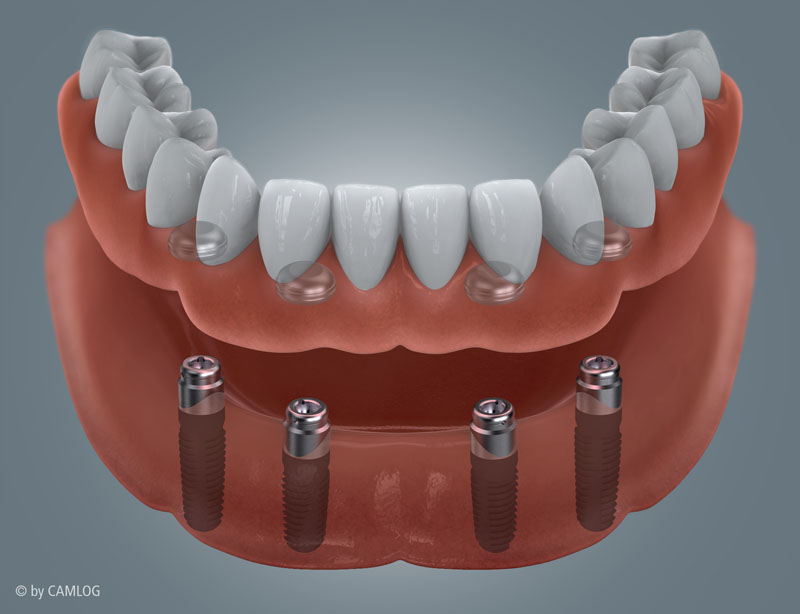

Mit den großen Fortschritten im Bereich der zahnärztlichen Implantologie wird der Traum nach festen Zähnen in vielen Fällen möglich mit dem Konzept "All on four/six".

Schematische Darstellung der Implantat- und Stegelemente